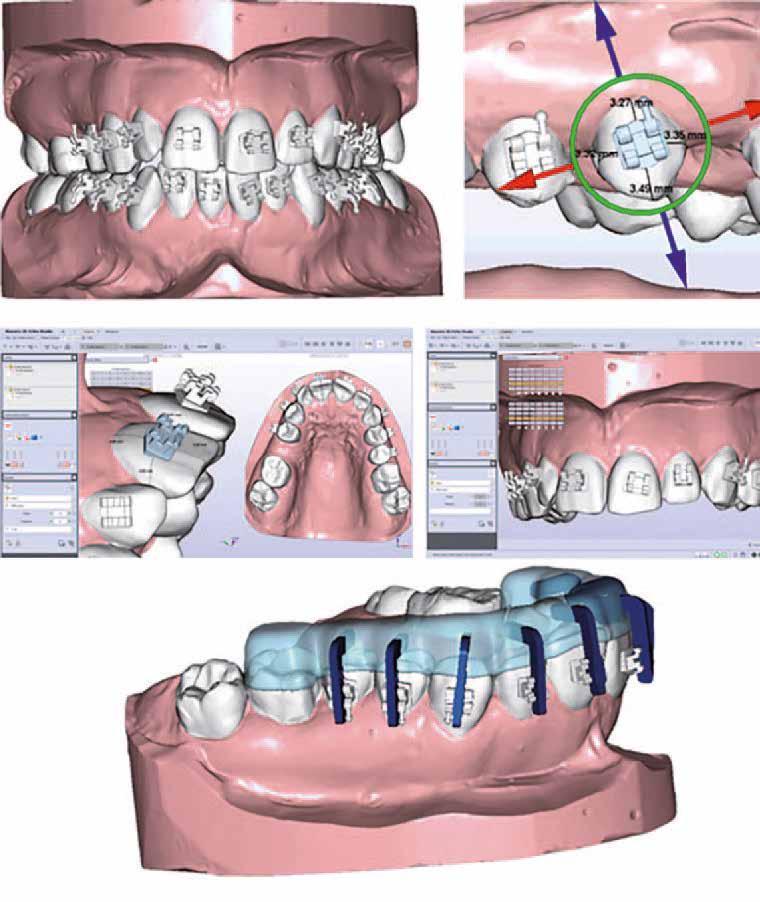

4 Tartalom ORTHODONTIA „Legfontosabb értéknek azt tartom, hogy sikerült átadnom a szakma iránti szeretetet, tudást, a páciensekhez való hozzáállást…” 8 Gyermekkori Class 2-es eltérés kétfázisú kezelése 24 Egy dilacerált gyökérrel rendelkező impaktálódott felső nagymetszőfog lézeres terápiával kiegészített orthodonciai kezelése 28 Szemfog és kisőrlő formázása kismetsző aplázia részárással történő kezelése során 36 Nyitott harapás kezelése miniimplantátumokkal 44 Az alignerekkel végzett esztétikai célú fogszabályozás határai 48 Klinikai digitális fényképezés a fogszabályozásban: professzionális fényképfelvételek a napi gyakorlatban 54 Tongue Star 2 (TS2) – a nyitott harapás-zárásnak hatékony eszköze 60 Temporomandibuláris betegségek (TMD) diagnózisa és az aquasplint terápia egy új eljárás a tmj/tmd egyszerű diagnózisához és hatékony terápiájához 68 Sablonnal történő bracket-ragasztás 72 Erős fogak és egészséges száj – meggyőző mosoly 76

A kezelés első lépéseként az összes maradó fogra breketteket rögzítettünk. A felső fogív nivellálása, a ferde tengelyállá-

sok korrigálása, valamint az impaktálódott fog előtöréséhez szükséges hely megteremtését követően, egy merev acél ív segítségével stabilizáltuk a fogakat. Ezt követően elvégeztük a jobb felső nagymetszőfog sebészi feltárását. A fog koronáját csupán lágyrész borította, ezért nem volt szükség a csontállomány elvételére. A felszabadítás során egy 975

nm-es hullámhosszon pulzáló üzemmódban alkalmazott lézert használtunk (LaserHF standard, Hager & Werken). A teljesítménye 3 W, az aktív ciklus-idő 50%-os, a vezetőszál átmérője pedig 0,4 mm volt (2. ábra). A lézert 150 másodpercen keresztül alkalmaztuk. A fogat borító lágyrészek eltávolítását követően egy láncos brekettet rögzítettünk a metszőfog bukkális felszínére. A műtétet követően nem tapasztaltunk vérzést, nem alakult ki oedema, valamint a páciens sem számolt be fájdalom vagy bármely egyéb kellemetlenség fennállásáról. A felszabadítást követően a páciens minden hónapban háromszor jelent meg a felszabadított területre ránövő lágyrészek és az íny lézeres eltávolítása céljából. A beavatkozások során ugyanazt a lézer készüléket használtuk, mint amivel a felszabadítást végeztük. Közvetlenül a felszabadítást követően megkezdtük a fog finom extrudálását a láncos breketthez kötött füzérgumi segítségével.